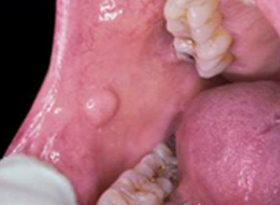

"OralID's fluorescence technology uses a blue light that helps me and my team members save lives by identifying cancerous and precancerous lesions in their early stages," says Dr. Schultz, "The screening does not involve any pain, discomfort, needles, or other frightening procedures—just a fluorescent blue light."

"If you find something suspicious like a bump, sore or color change in the tissue of your mouth, lips or tongue, don't wait until your next scheduled appointment. Call us and come in as soon as possible," Dr. Schultz advises.